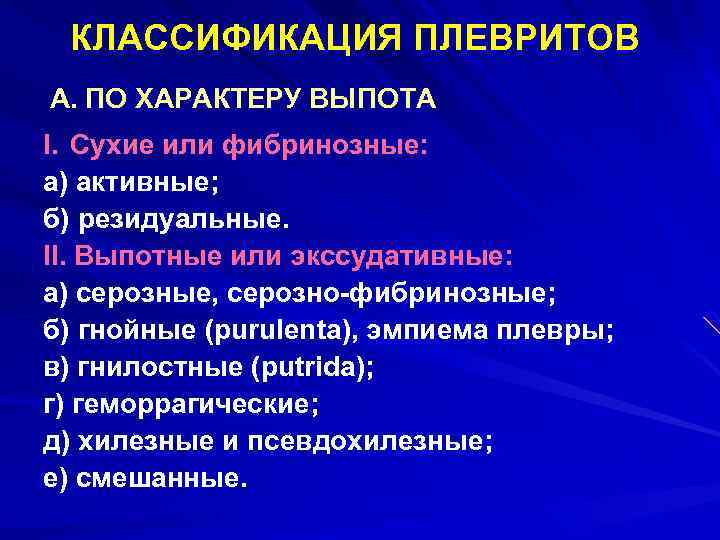

Дифференциальная диагностика заболеваний плевры